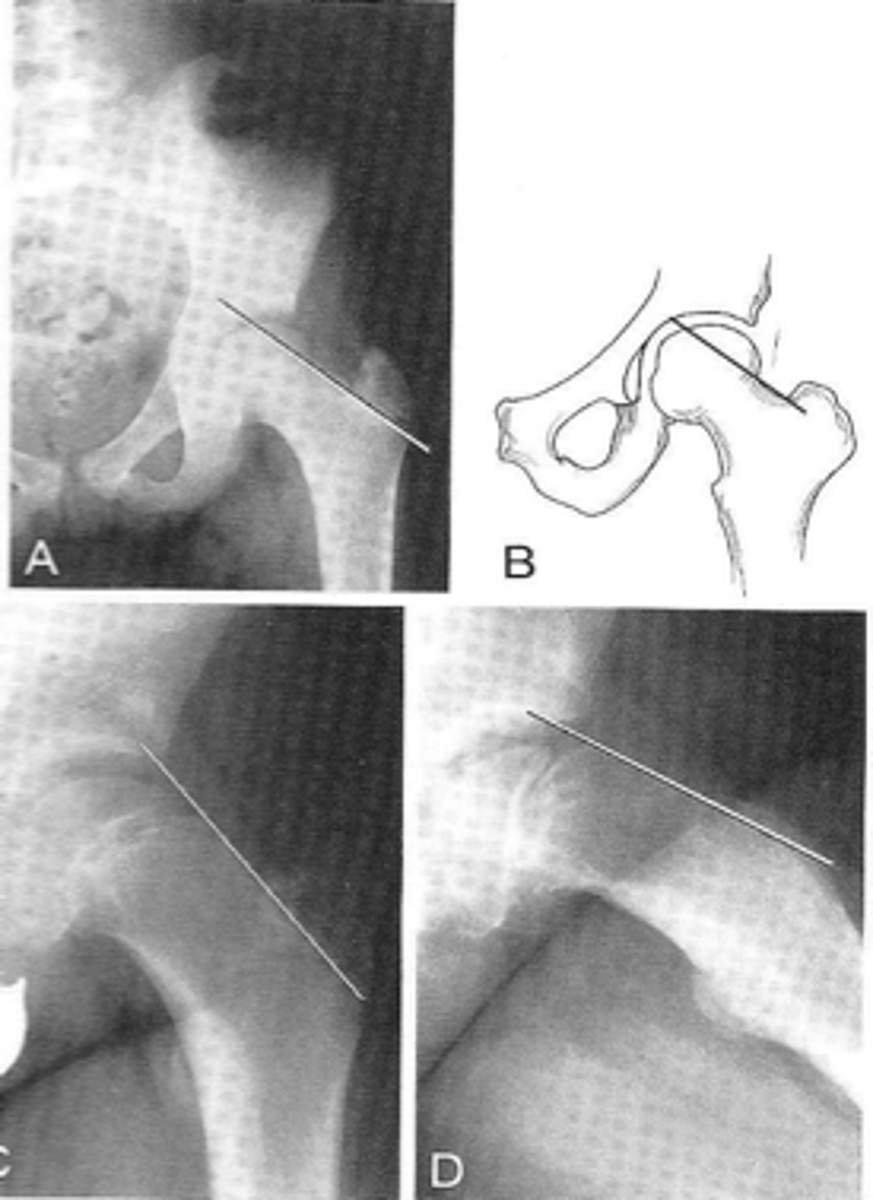

Shenton's line

ID measurement

<p>ID measurement</p>

- AP hip

- AP pelvis

What views are used to see Shenton's line?

<p>What views are used to see Shenton's line?</p>

- Smooth arc along femoral neck

- Obturator foramen

Shenton's line landmarks

<p>Shenton's line landmarks</p>

Continuous and smooth

Shenton's line normal measurements

<p>Shenton's line normal measurements</p>

- Hip dislocation

- Femoral neck fracture

- Slipped epiphysis

Clinical significance of Shenton's line

<p>Clinical significance of Shenton's line</p>

Skinner's line

What views are used to see Skinner's line?

<p>What views are used to see Skinner's line?</p>

- Mid-axis of femoral shaft

- Right angle tangent to tip of greater trochanter

Skinner's line landmarks

<p>Skinner's line landmarks</p>

Fovea capitis should lie above or at level of trochanteric line

Skinner's line normal measurement

<p>Skinner's line normal measurement</p>

Fracture or other causes of coxa vara

Clinical significance of Skinner's line

<p>Clinical significance of Skinner's line</p>